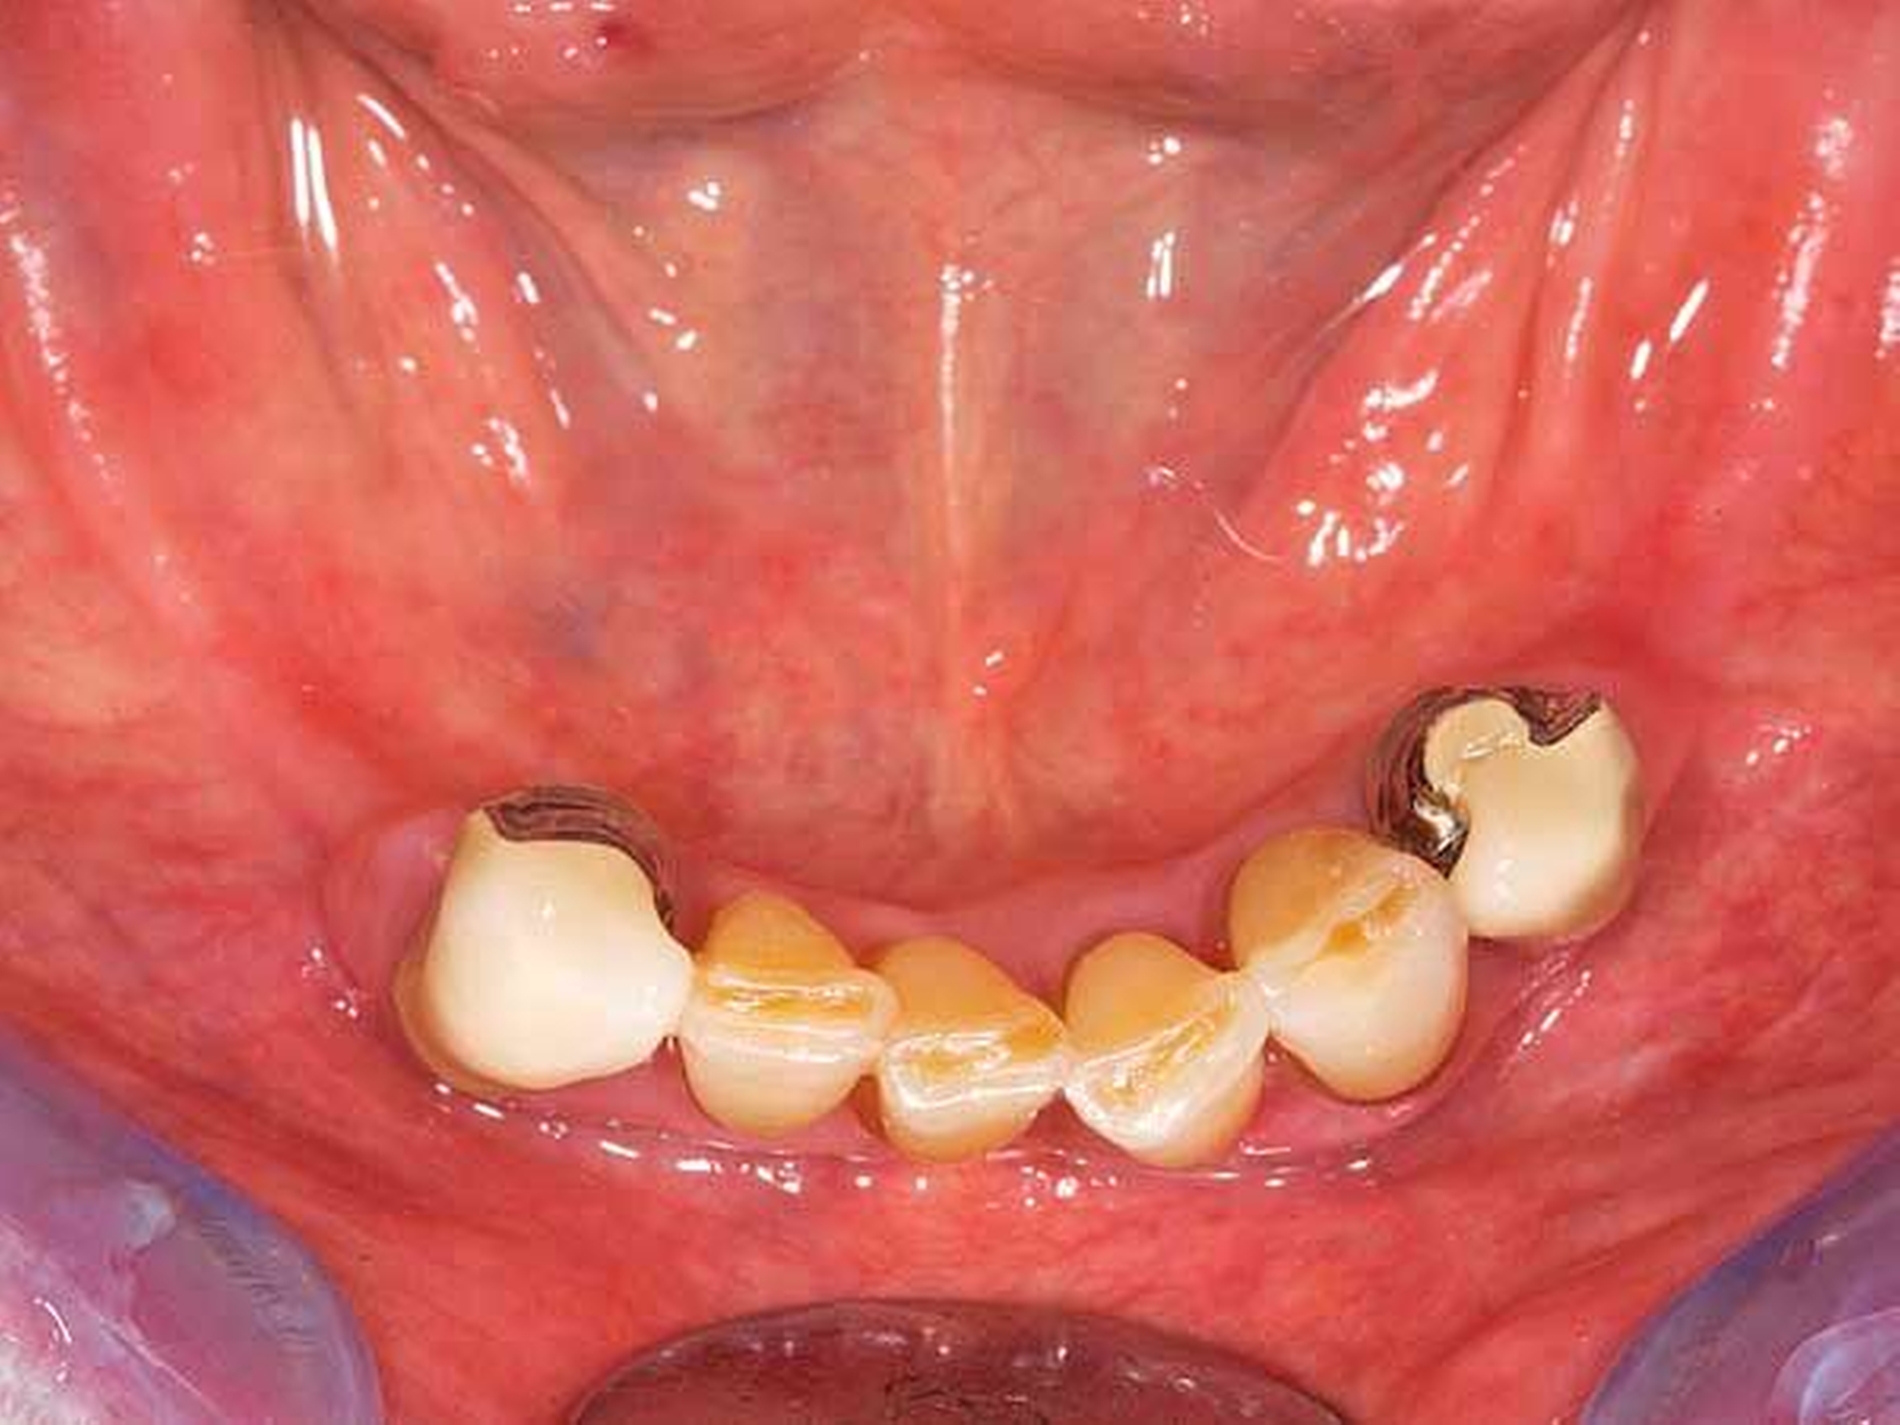

Das Orthopantomogramm (Abbildung 7) zeigt die Gebisssituation eines 89-jährigen Patienten mit kardiovaskulärer Anamnese (Herzinfarkt, Stent-Implantate) und deutlich reduziertem, fast hinfälligem Allgemeinzustand. Der Patient erhält 14(!) verschiedene Medikationen. Der überweisenden Kollegin erschien die Behandlung in der Praxis zu riskant. Nach Abschluss der Extraktionstherapie stellte sich der Patient zur prothetischen Beratung und Weiterversorgung an unserer Poliklinik vor. Im Oberkiefer wurde ein totaler Zahnersatz geplant. Im Unterkiefer verblieb ein karies- und füllungsfreies Restgebiss von 33 nach 42 (Abbildung 8). Aus gesundheitlichen Gründen schied eine Präparation der karies- und füllungsfreien Zähne für die Aufnahme von Doppelkronen oder metallkeramischen Kronen mit oralen Fräsungen aus.

Front- und Eckzähne sind aufgrund ihrer Anatomie grundsätzlich schlecht für die Aufnahme von Gussklammern geeignet. Die Lösung in diesem zweiten Fall bestand in der Anwendung zweier geteilter Klammern (Roach-Klammer), ausgeführt als Druckanker (Abbildungen 9 und 10). Lingual wurden die Zähne 33 und 42 mit den oralen Klammerarmen großflächig von disto- nach mesioapproximal gefasst. Gegebenenfalls müssen, nach Augenmaß senkrecht zur Einschubrichtung, die Tuberculi und der distoapproximale Kontaktpunkt im Schmelz mit einem Diamantfinierer leicht abgeflacht werden. Die Präparation für die orale Klammerauflage in Höhe der Tuberculi muss konsequent als Stufe von 1 mm Tiefe parallel zur Okklusionsebene eingeschliffen werden. Die Auflage selbst ist in den oralen Klammerarm integriert. Die vestibulären Retentionsarme liegen dem Zahn nicht passiv an, sondern stehen unter Vorspannung und drücken den Ankerzahn bei eingegliedertem Zahnersatz aktiv gegen das starre Widerlager der oralen Umfassung. Dies sichert in Verbindung mit der weiten, fast geschiebeartigen oralen Fassung und der integrierten Klammerauflage eine akzeptable Kippmeiderfunktion.